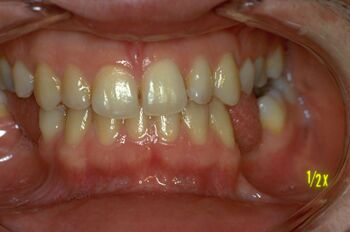

The clinical example of a patient who underwent orthognathic surgery (Figure 2) demonstrates how an apparently "normal" occlusal condition can conceal severe trigeminal system anomalies, revealed only through advanced electrophysiological tests. Conversely, a patient with clear signs of malocclusion (Figure 1) might present a more balanced neurophysiological profile. These findings suggest that macroscopic observable reality may not fully reflect the deeper state of the system.

In the first chapter 'Introduction' we have already mentioned the patient in figure 1 in which it would be irreverent towards the orthodontics discipline not to consider a state of 'Malocclusion' but in some way we have also questioned the 'Axiomatic Information' by replacing the classic orthodontic dogma with a neurophysiological vision of the system status of the patient. From this approach it was clear that mesoscopic reality is very different from macroscopic reality to which, we are used to.